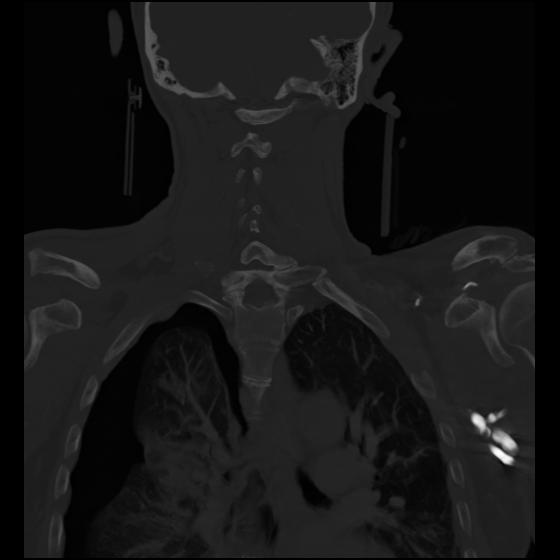

23 ANGIO,CE,Cor-MIP,5.000,ANGIO,Cor-MIP,